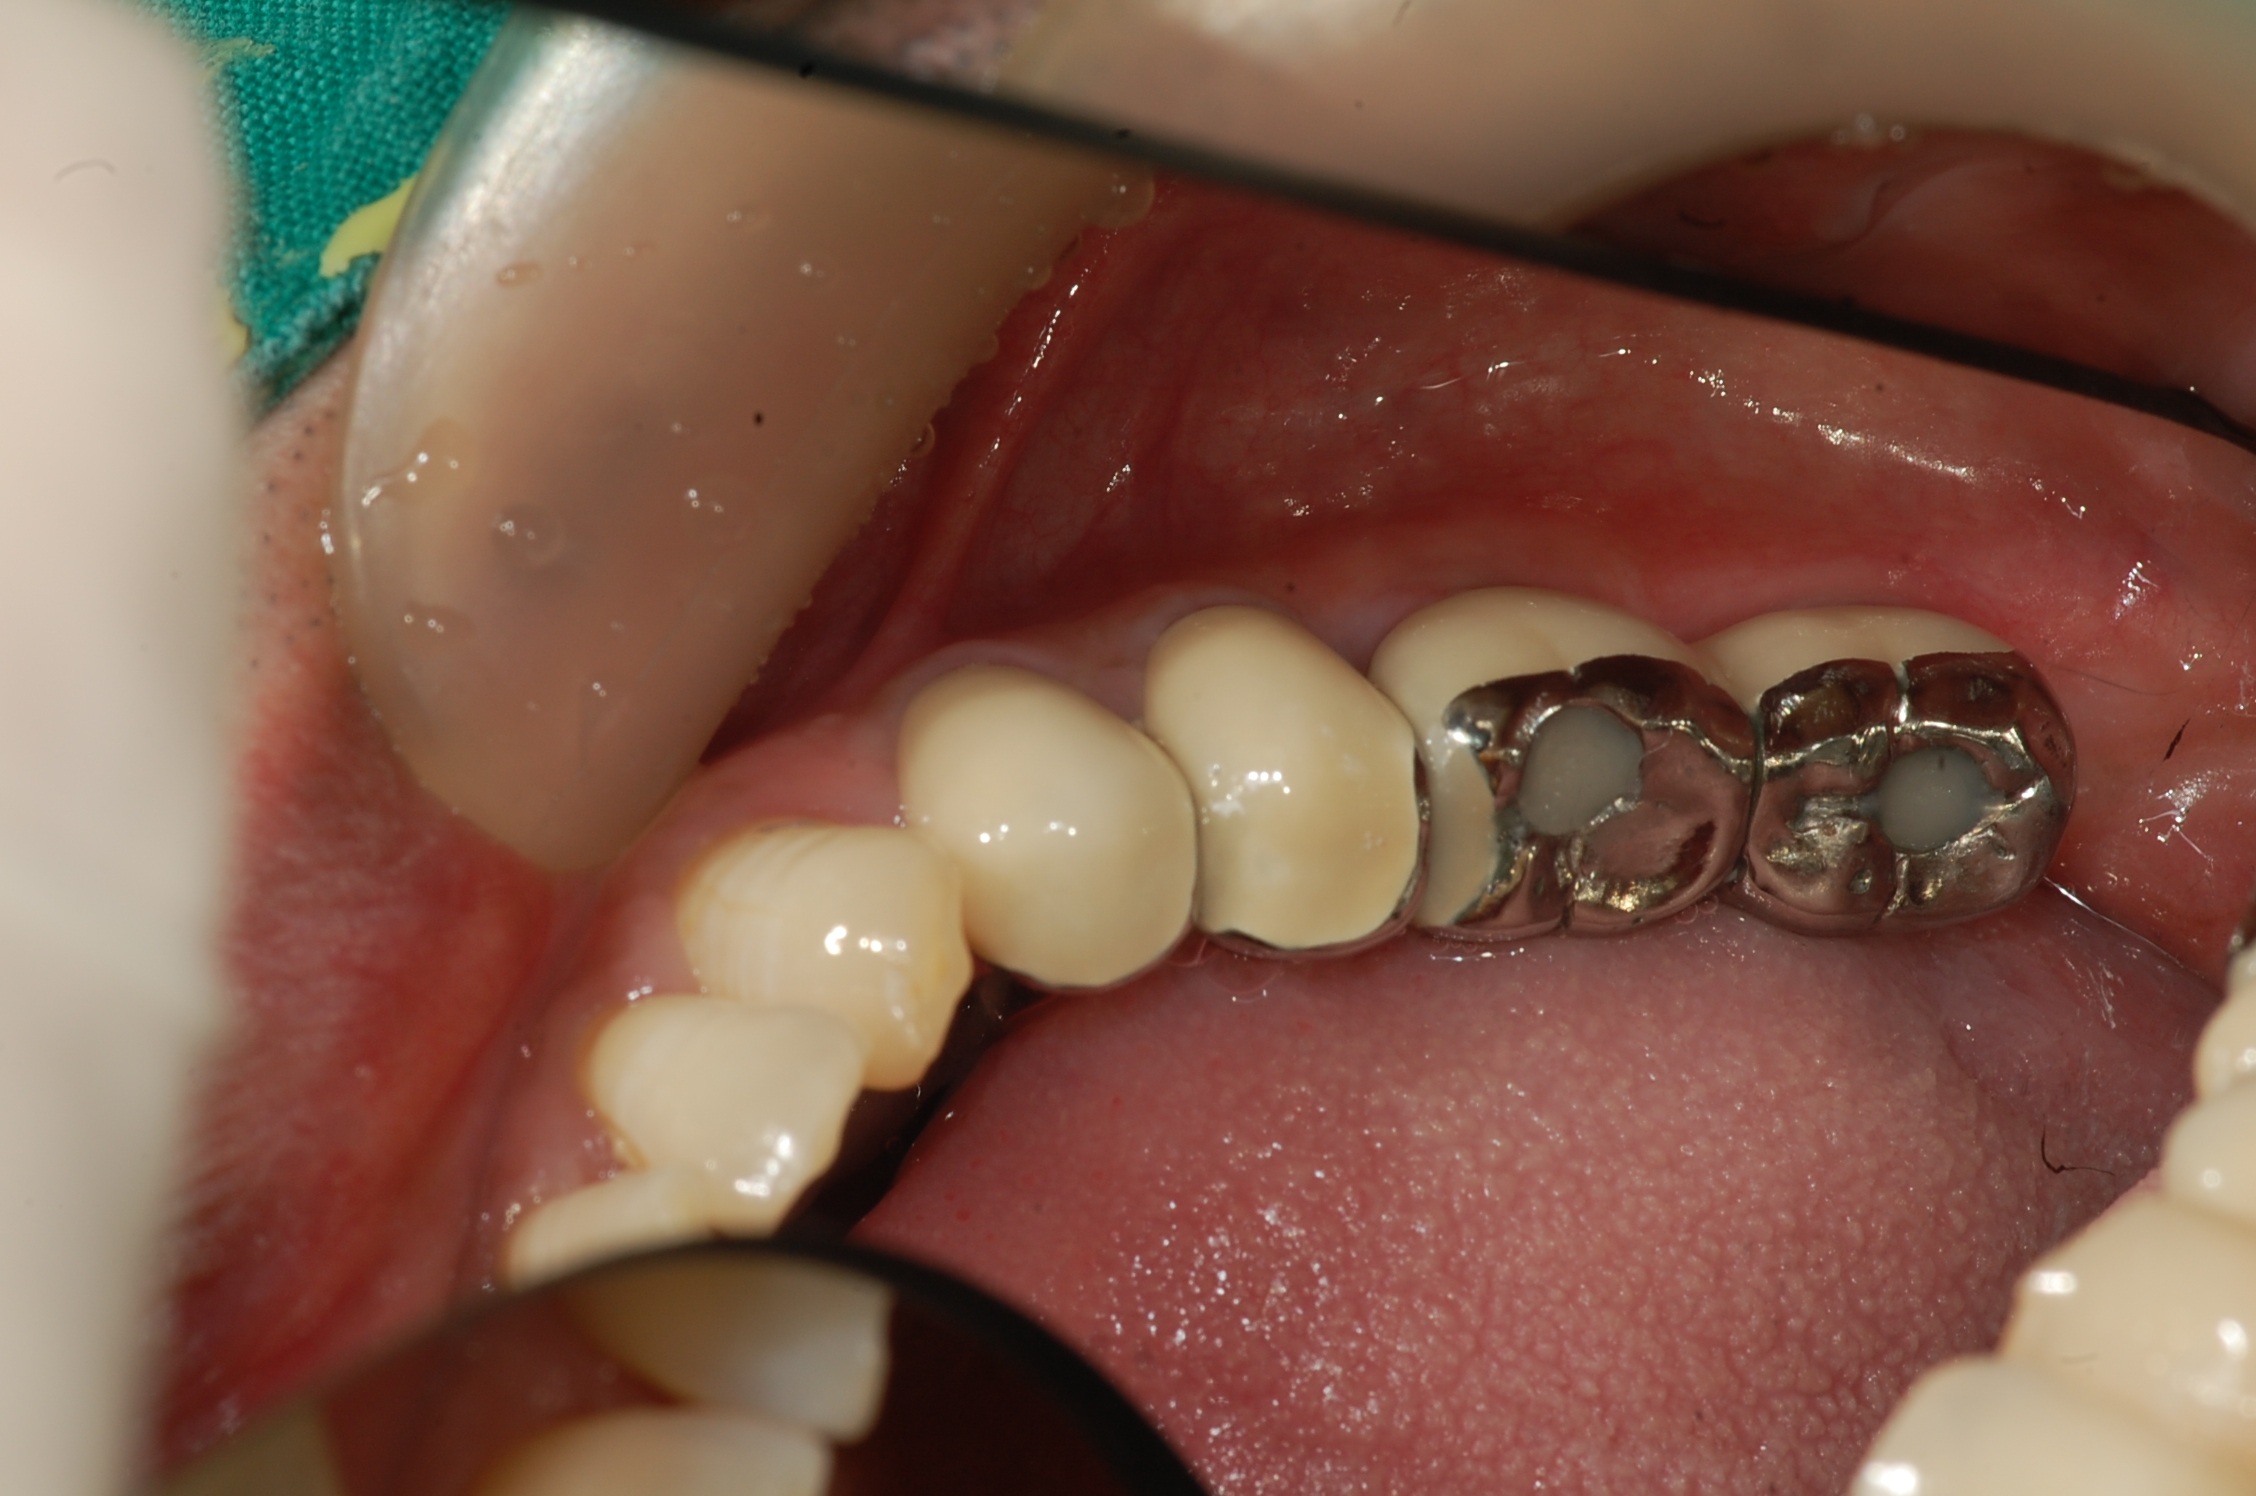

[임플란트] 제목 : 하악구치부

임플란트 및 보철치료